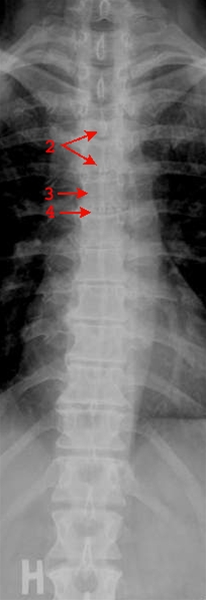

Torakalcolumna, forfra

Normalt frontalbillede af torakalcolumna (rygsøjlen i brystkasseniveau)

• 2. Processus spinosus

• 3. Hvirvellegeme, corpus vertebrae

• 4. Diskus